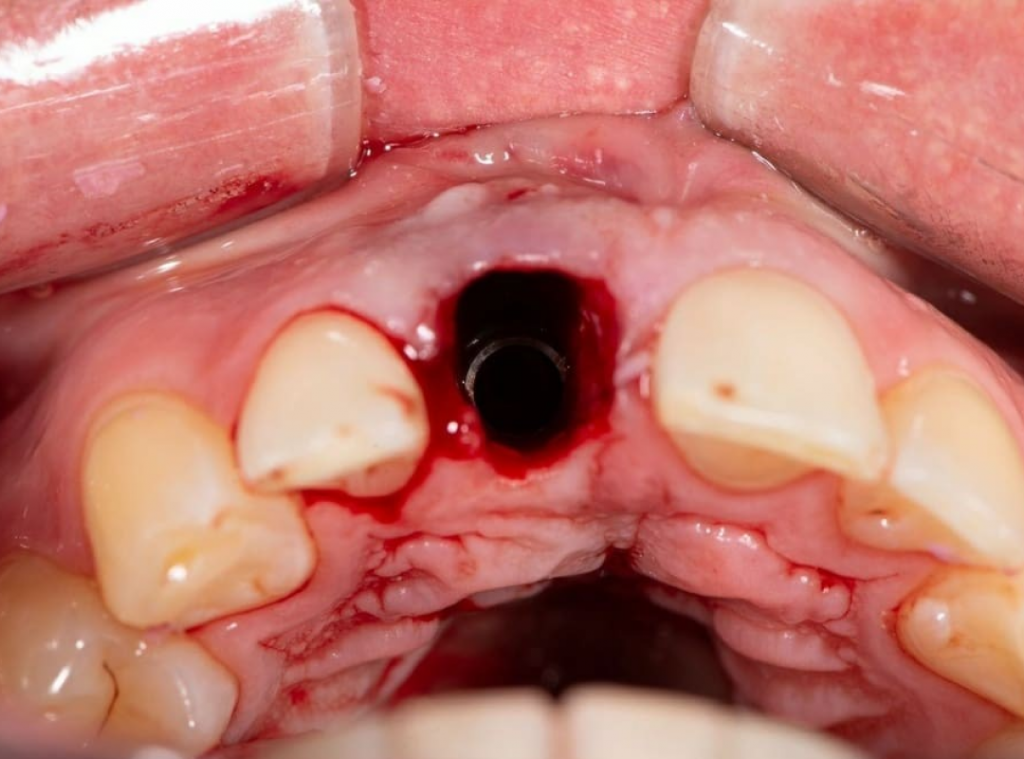

Имплантация AnyRidge во фронтальном отделе.

Пациент обратился с жалобами на эстетический вид центрального резца, небольшую подвижность и систематически появляющийся свищевой ход над зубом.

На КТ была обнаружена трещина корня, не позволяющая вылечить зуб. Было принято решение об удалении зуба с одномоментной имплантацией. Коронковую часть временного зуба восстановили из родного зуба пациента, предварительно отреставрировав его перед установкой.